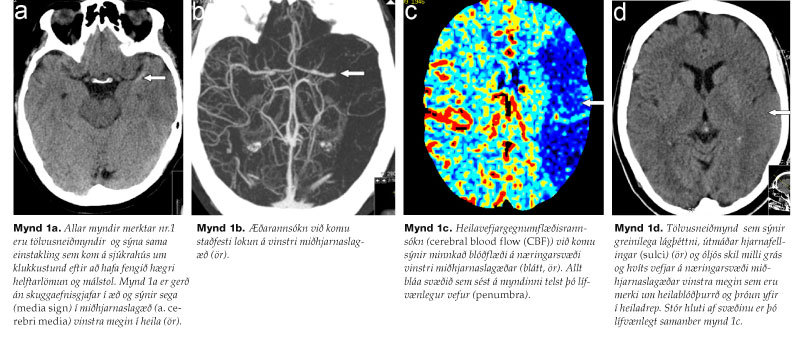

Myndrannsóknir gegna lykilhlutverki við greiningu heilablóðfalls. Í dag er langalgengast að beita tölvusneiðmyndatöku án skuggaefnis sem útilokar blæðingu á skjótan og öruggan hátt. Stundum getur slík rannsókn sýnt aukna þéttni í slagæð, svokallað hyperdense-teikn vegna sega í æðarholinu. Ef seginn er staðsettur í miðhjarnaslagæð (a. cerebri media) kallast teiknið media sign (mynd 1a). Rannsóknin getur einnig sýnt snemmkomin teikn um drep, svo sem lágþéttni (hypodensity) heilavefjar, bjúgmyndun, eða óljós skil milli gráa og hvíta efnisins (mynd 1d).5 Einnig er hægt að framkvæma æðamyndatöku (CT angiography) til að leita eftir slagæðaþrengingum og -lokunum (mynd 1b).6 Þá getur heila-vefjargegnumflæðisrannsókn (cerebral perfusion) verið gagnleg. Með þeirri rannsókn er hægt að meta stærðina á lítt starfshæfum en lífvænlegum heilavef (penumbra) (mynd 1c) í samanburði við svæði þar sem drep hefur orðið. Þegar svæði lífvænlegs heila-vefjar er tiltölulega stórt er til mikils að vinna.7 Þó skal tekið skýrt fram að eingöngu þarf hefðbundna tölvusneiðmyndarannsókn til undirbúnings segaleysandi meðferðar. Hinar rannsóknirnar sem nefndar voru geta varpað skýrara ljósi á ástand heilavefjar sem hefur orðið fyrir blóðþurrð og gefið upplýsingar um lokun slagæðar. Aðalatriðið er þó alltaf að gefa segaleysandi meðferð sem fyrst.